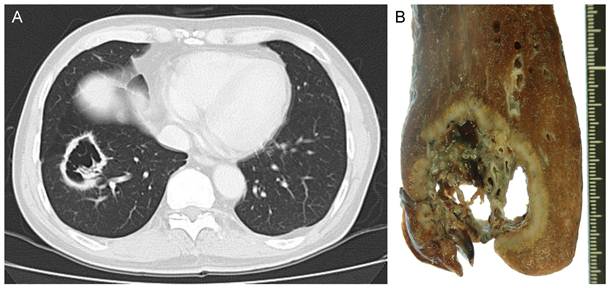

The patient was a 60-year-old man with a history of smoking 10 cigarettes per day for 35 years. He was found to have a small shadow in the right lower lung field on chest X-ray in 2006, and was thereafter followed-up at another hospital (Figure 1A). Chest X-ray in 2007 revealed a cavitating shadow at the same site (Figure 1B). A chest X-ray in 2008 showed thickening of the cavity wall, and that in 2009 revealed the tendency of the entire cavity shadow to enlarge (Figure 1C, D). He was referred to our department. Computed tomography showed an inhomogeneous thickening of the cavity wall and spiculation from the tumor margin, as well as the presence of lung structures in the cavity (Figure 2A). Bronchoscopic biopsy of the cavity wall led to a diagnosis of adenocarcinoma. Under a diagnosis of lung cancer (cT2aN0M0), right lower lobectomy with hilar and mediastinal lymph node dissection was performed.

Figure 1

Chest X-ray findings. A, B, C, and D show chest X-rays taken in 2006, 2007, 2008, and 2009, respectively. These X-rays revealed a lesion in the right lower lung field, which formed a cavity and enlarged over time.

Figure 2

Radiologic and macroscopic findings. A, Computed tomography showed a cavitary shadow in the basal segment of the right lung, and the cavity contained lung tissue. B, Macroscopically, the cavity was torn in some areas, and lung tissue and blood vessels could be observed in the cavity.